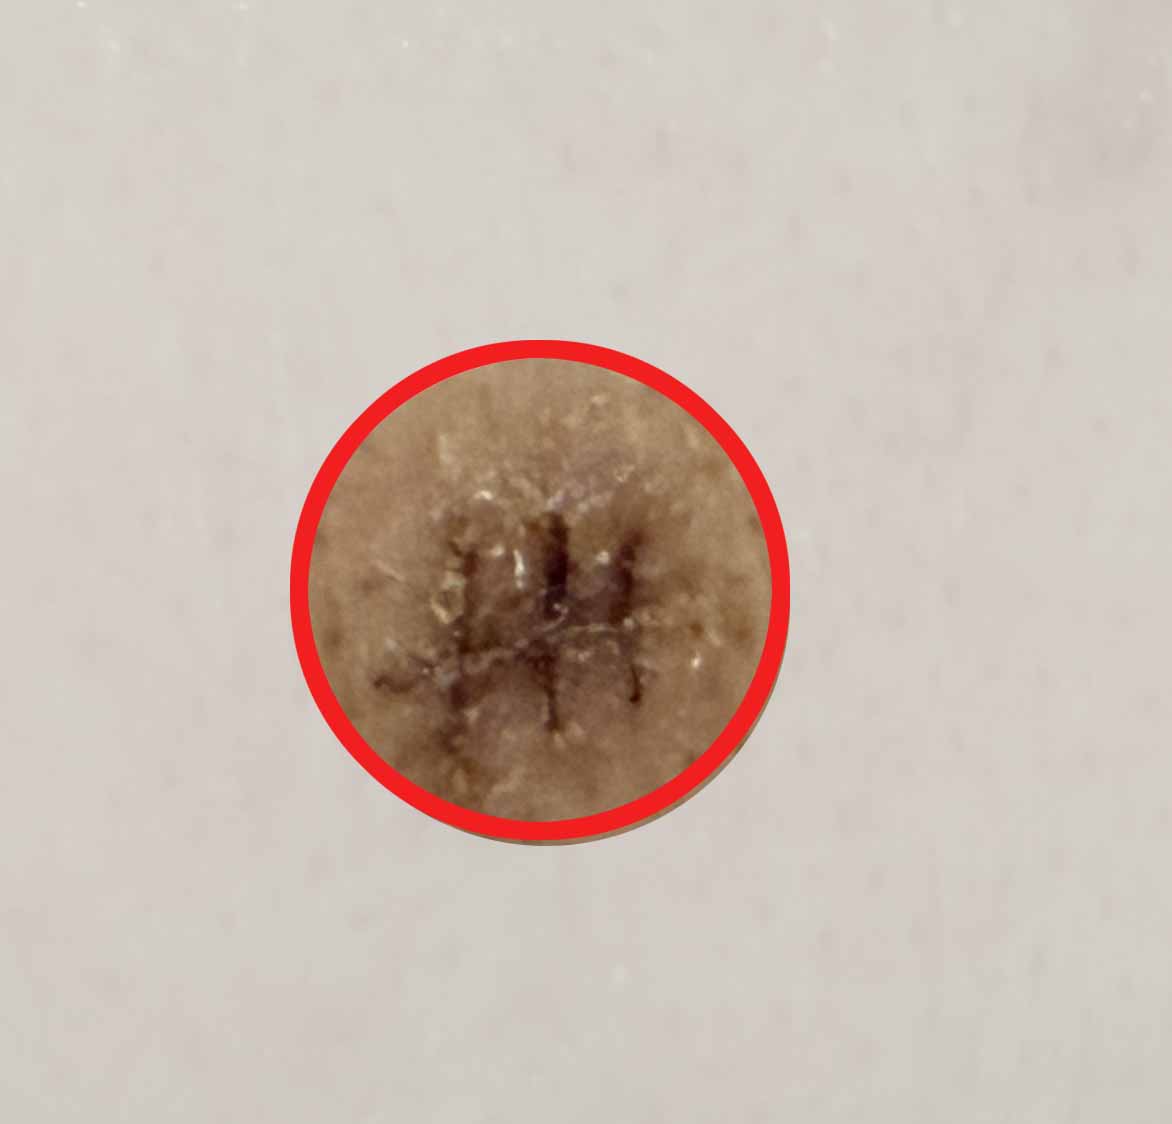

| 🩸 제거된 피지낭종

등에 있던 건 수년간 누적된 상태라 꽤 큰 크기였어요. 안에 딱딱한 피지 찌꺼기와 검은 부분이 있었고, 제거한 조직은 병리 검사에 보냈지만 다행히도 양성 피지낭종이었습니다.

📸 제거된 피지낭종과 수술 부위 사진

※ 아래 더보기 사진은 실제 수술 중 제거된 피지낭종 사진입니다. 불편하신 분은 열람을 삼가 주세요.

제거한피지낭종피지낭종제거-수술부위-턱피지낭종제거-수술부위-등

제거된 피지낭종 / 제거부위 수술사진-턱 + 등